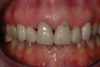

A patient presented with two defective 3-unit fixed partial dentures spanning teeth Nos. 6 through 8 and teeth Nos. 9 through 11 (Figure 7). The defective fixed partial dentures were removed (Figure 8), an impression was made, and traditional provisional fixed partial dentures without ovate pontics were placed. After the impression was sent to the laboratory, the lab technician prepared ovate pontic sites on the stone cast (Figure 9) and fabricated the new definitive bridges. On the day of insertion, the provisional fixed partial dentures were removed (Figure 10), ovate pontic sites were prepared using a teardrop-shaped diamond bur (Figure 11), and the sites were sounded to confirm that there was at least 2 mm from the base of the pontic site to the alveolar bone (Figure 12). The fixed partial dentures were cemented, and the postoperative healing was uneventful (Figure 13).

(13.) Close-up retracted 2-month postoperative view of the final fixed partial dentures spanning teeth Nos. 6 through 8 and teeth Nos. 9 through 11, along with replacement crowns for the other restored maxillary teeth.

Figure 13